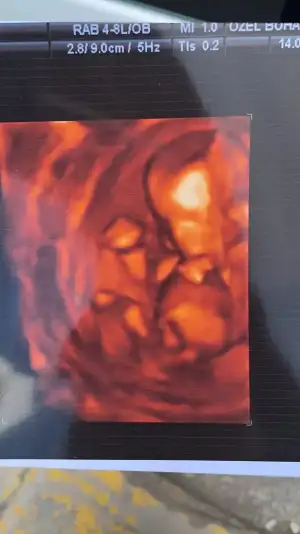

Tülperdede kız dedi ikrameyra da kız dedi Bi göstermedi şeyini sıpamKayınvalidemin teorisine göre kız görünüyor

Kayınvalidemin 11 tane kendi doğurmuş bi o kadar da doğum görmüş. kızlarının, gelinlerinin bebeklerinin cinsiyetini hep anlamış ultrasondan. Buna da kız derdi

AyyyyBunu tam seçemedim canımkayınvalidemin yanına gidebilirsem gösteririm ona

Kayınvalidemin teorisine göre kızsağlıkla kucağınıza alın inşaallah.

Kayınvalideme göre Kız görünüyor sağlıkla gelsin

Erkeğe daha yakın ama emin değilimEki Görüntüle 2896308 merhaba bana da yorum yaparmisiniz